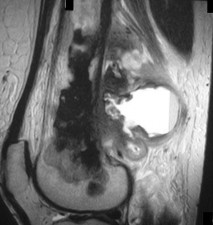

A 15-year-old male presents with deep knee pain awakening him at night. Radiographs show a permeative destructive lesion in the distal femoral metaphysis with a 'sunburst' periosteal reaction and Codman's triangle.

Biopsy confirms high-grade conventional osteosarcoma. What is the most critical prognostic factor for long-term overall survival in this patient?

Explanation

For localized high-grade osteosarcoma, the most important prognostic indicator is the histologic response to neoadjuvant chemotherapy. This is evaluated during the definitive resection. A 'good response' is typically defined as greater than 90% or 99% tumor necrosis. Patients who achieve this level of necrosis have a significantly improved disease-free and overall survival rate compared to 'poor responders' who have extensive viable tumor cells remaining.